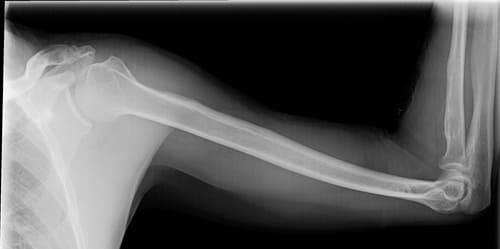

- рентгенографию плечевой области, кости, а также преплечья, локтя;